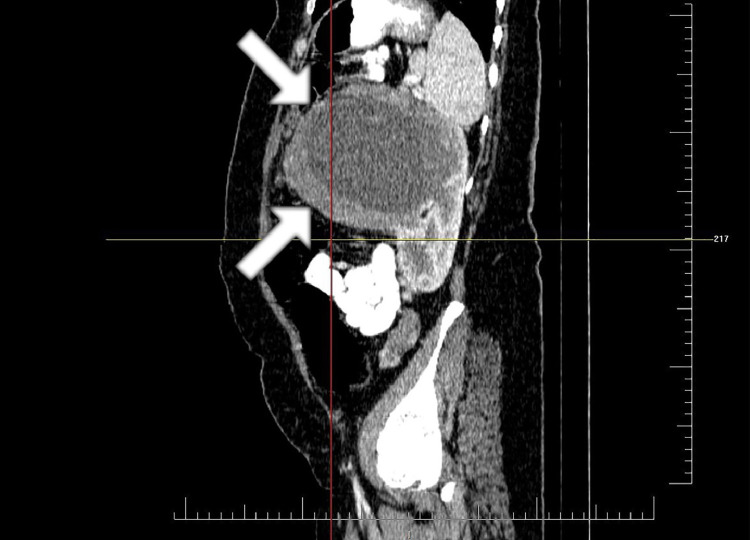

Fig. 2.

The sagittal view of tumor in abdominal CT. The upper limit of tumor is at the level of pancreatic body. The lower limit of tumor is at the level of midpart of left kidney. The tumor mostly grows anteriorly with exophytic pattern. The boundary of the tumor is shown with the white arrow. CT, computed tomography.